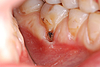

Cette dent présente une récession gingivale qui a favorisé l'apparition d'une carie.

La réalisation d'une greffe gingivale a permis de protéger la racine et de préserver l'avenir de la dent.